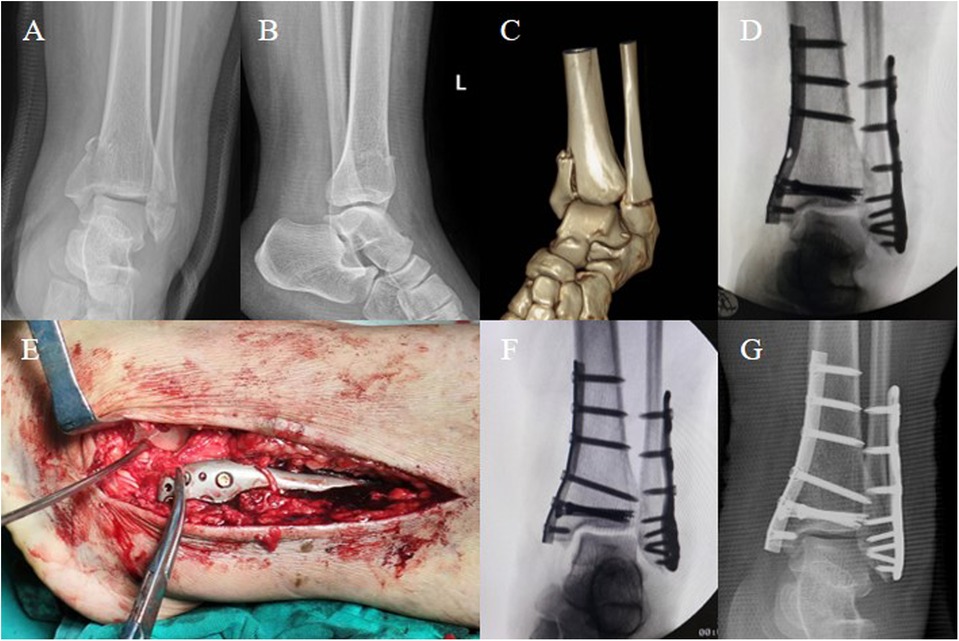

A 31-year-old Asian female (BMI: 30.4 kg/m2) sustained a left ankle sprain from a misstep two days before presentation, resulting in swelling, pain, and limited mobility. She underwent an examination at a local hospital, where DR images indicated fractures of the left medial and lateral malleoli. Seeking further treatment, she visited our hospital. She has an otherwise healthy medical history. Physical examination revealed grade 3 swelling in the left ankle joint, significant tenderness in both the medial and lateral malleoli, limited joint movement due to pain, normal dorsalis pedis pulse, and good distal toe perfusion. DR and CT images of the ankle showed a transverse fracture of the distal fibula and a vertical fracture of the medial malleolus (Figures 1A–C), consistent with a SAD fracture as per the Lauge-Hansen classification. No neurovascular injuries were found. Preoperative diagnosis was a left bimalleolar fracture, with a plan for surgical intervention.

Figure 1. A 31-year-old Asian female (BMI: 30.4 kg/m2) sustained a left ankle sprain, and preoperative imaging diagnosed a bimalleolar fracture. (A–C) Preoperative DR images and CT scans show fractures of the medial and lateral malleolus in the left ankle, classified as SAD stage 2 according to the Lauge-Hansen classification. (D) Intraoperative fluoroscopy after stabilizing the medial and lateral malleoli indicates poor reduction of the talus, with a Talar Tilt angle (TT angle) of 6.5°. (E) Extension of the lateral incision revealed rupture of ATFL, with only a small amount of ineffective ligament fibers present. (F) The lateral ligaments were repaired using the Broström-Gould technique, and fluoroscopy showed satisfactory reduction of the talus and proper alignment of the ankle joint, with a TT angle of 0.5°. (G) Postoperative anteroposterior DR image demonstrates satisfactory positioning of the internal fixation and good alignment of the ankle joint.

Under spinal anesthesia, the patient was positioned supine. After routine disinfection and application of a tourniquet on the left lower limb, a medial incision was made at the left ankle to expose the distal tibia, revealing a comminuted fracture of the medial malleolus with bone fragment separation. The distal medial tibial articular surface was cleaned, and the fracture was reduced under direct vision, temporarily fixed with Kirschner wires. Fluoroscopy confirmed satisfactory reduction. A one-third tubular plate (Zhengtian, China) was used for fixation, reinforced with two 4.0-mm cannulated screws (Zhengtian, China). Subsequently, a lateral incision at the left ankle exposed a transverse fracture of the lateral malleolus. After reduction, it was temporarily fixed with Kirschner wires, and then secured with a lateral locking plate (Zhengtian, China) and multiple screws. C-arm fluoroscopy showed appropriate internal fixation, but the talus remained in varus tilt (Figure 1D). The anterior drawer test was positive. Considering the patient's history, physical examination, fracture classification, and intraoperative fluoroscopy, an ATFL injury was suspected. Thus, the incision was extended to explore further, revealing a ruptured ATFL entrapped in the tibiofibular joint space (Figure 1E). Then, a 3.0-mm bone anchor (Arthrex, USA) was placed at the tip of the lateral malleolus, and the ligament and superior extensor retinaculum were sutured using the Broström-Gould technique (to maintain eversion knotting). Fluoroscopy confirmed the correction of talar tilt and restoration of ankle congruence (Figure 1F). The surgical area was irrigated, stepwise sutured, the tourniquet released, and the wound dressed with alcohol gauze and externally stabilized with a plaster cast. The surgery was completed successfully, and the patient remained hemodynamically stable and was safely returned to the ward with adequate distal toe perfusion. Immediate postoperative DR images showed that, as during the surgery, the internal fixation was in a satisfactory position, and the ankle joint alignment was good (Figure 1G).